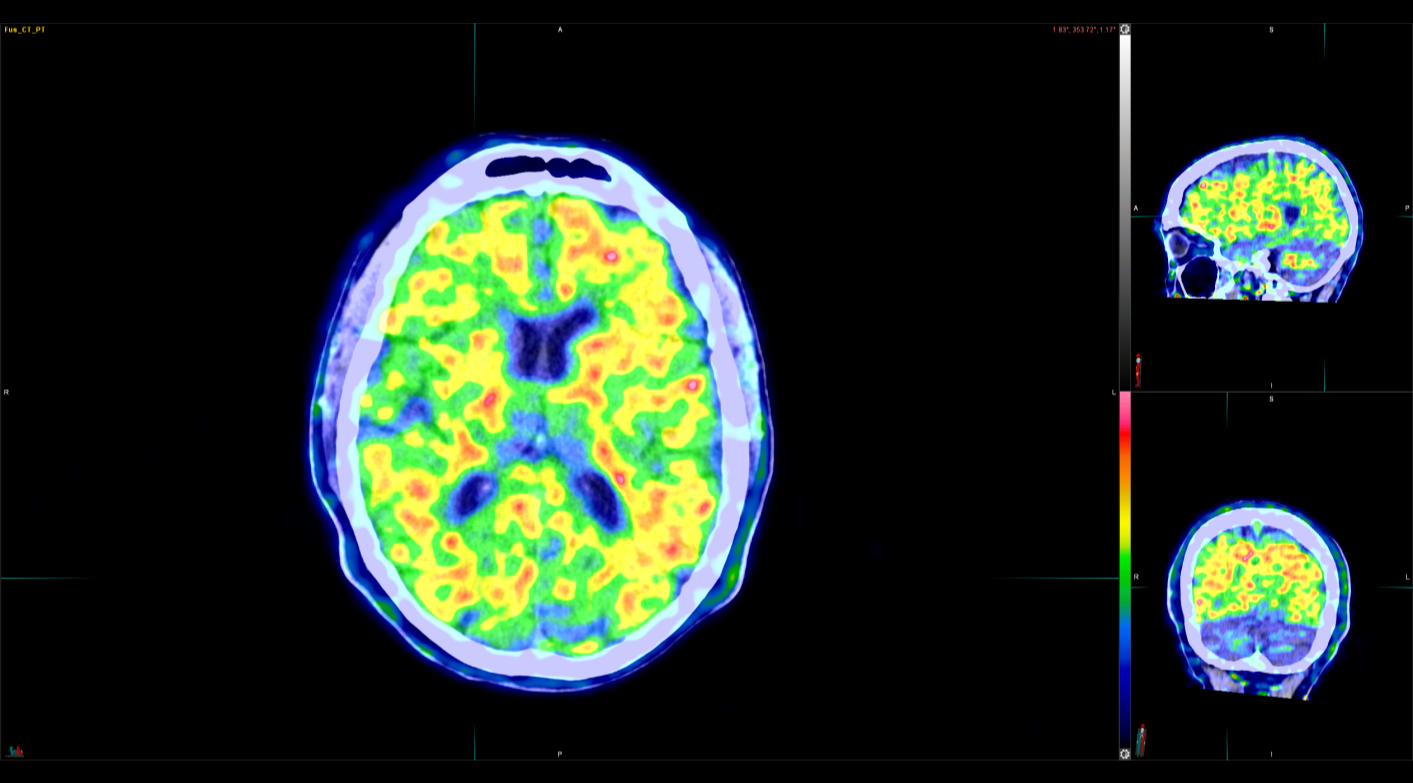

Η Τομογραφία Εκπομπής Ποζιτρονίων (PET) αποτελεί μια εξειδικευμένη μέθοδο της Πυρηνικής Ιατρικής που χρησιμοποιεί μοριακή απεικόνιση για να εντοπίσει και να παρακολουθήσει φυσιολογικές και παθολογικές λειτουργίες του οργανισμού. Συνδυάζοντας τη λειτουργική απεικόνιση της PET με την ανατομική πληροφορία της αξονικής τομογραφίας (CT), η υβριδική εξέταση PET/CT παρέχει εικόνες υψηλής ευκρίνειας και τη δυνατότητα ποσοτικής αξιολόγησης των βιολογικών μηχανισμών σε κυτταρικό επίπεδο.

Οι κυριότερες εφαρμογές της αφορούν την ογκολογία, τη νευρολογία και, σε μικρότερο βαθμό, την καρδιολογία, ενώ συνεχώς αναπτύσσονται νέες χρήσεις σε άλλες ιατρικές ειδικότητες.

Στο Κέντρο PET/CT πραγματοποιούνται εξειδικευμένες εξετάσεις που καλύπτουν ένα ευρύ φάσμα κλινικών εφαρμογών στη σύγχρονη Πυρηνική Ιατρική. Ανάλογα με το είδος του προβλήματος και τη φύση της νόσου, χρησιμοποιούνται διαφορετικά ραδιοφάρμακα για τη μελέτη συγκεκριμένων βιολογικών μηχανισμών.